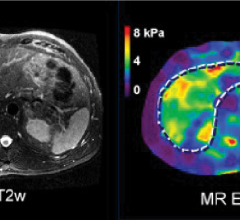

August 9, 2022 — Bot Image, an Omaha-based MRI medical device company has developed an AI-driven medical device CAD ...